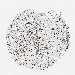

BRCA TCGA BRCA VALIDATION PROTEIN EXPRESSION

ANTIBODIES

AND

VALIDATION